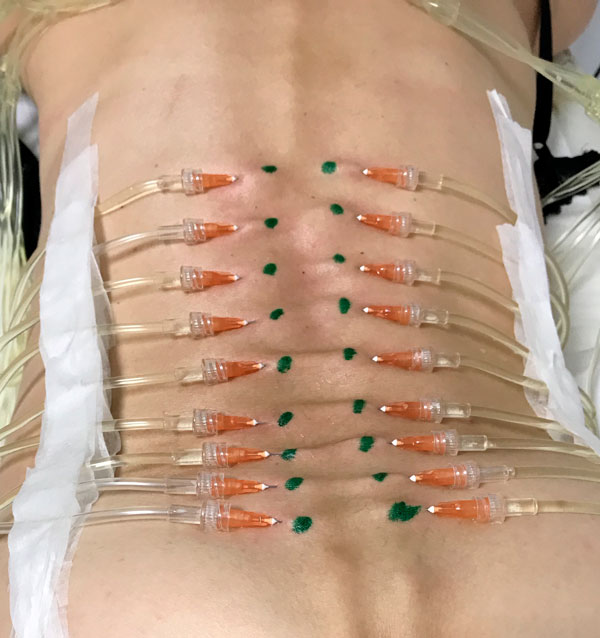

L’hypodermoclyse ou perfusion sous-cutanée continue ou discontinue de grandes quantités de sérum physiologique et de médicaments, effectuée par des infirmier(ères) en ville, à l’hôpital ou en EHPAD.

Le « coussin d’hydrotomie » constitue un véhicule d’apport thérapeutique selon son volume d’injection, entre les plans profonds et superficiels dans le cadre de l’AMM, du sérum physiologique (Nacl 0,9%).

- La profondeur de l’injection sous cutanée (12mm) ou intra dermique (4mm) selon la région concernée : rachis, épaule, genoux, doigts…

- Le volume d’injection entre 5ml et 500ml.

Toujours selon les mêmes critères l’injection varie :

- De l’injection simple à plusieurs injections,

- Pouvant évoluer à la perfusion sous cutanée multipoints pour des grandes surfaces (mésothérapie de surface : rachis)